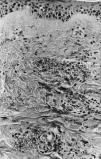

Se realizó biopsia cutánea para estudio histopatológico y cultivo. En 48 horas se recibieron los cultivos en sangre y piel con crecimiento de Trichosporon asahii, por lo que se añadió fluconazol al tratamiento. La paciente quedo afebril, pero se mantuvo la pancitopenia, con disnea y anuria, falleciendo 5 días después. El estudio histológico confirmó el tromboembolismo micótico que ocupaba la luz y pared vascular, que con la tinción de PAS ponía de manifiesto numerosas hifas y conidias (Figs. 3 y 4).

FIG. 4.--Hifas en luz vascular y zona extravascular. (PAS, ×400.)